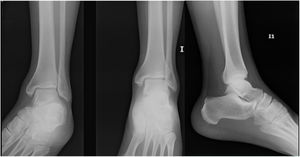

En el caso 2 se estableció como criterio quirúrgico el espacio claro medial aumentado de 5mm y la diferencia de 5 grados de el ángulo talocrural como se observo en las figuras 4 y 5,

En momentos diferentes, se entregó a cada participante del estudio una serie con los cuatro casos, todos evaluados mediante una serie de trauma unilateral y nuevamente, pero en un momento diferente de tiempo, los mismos cuatro casos con las mediciones radiológicas explícitamente escritas y realizadas debidamente con comparación del lado contralateral sin decirle al participante que eran los mismos cuatro casos iniciales de las series de trauma unilateral.

Denominamos grupo de estudio a la serie radiográfica unilateral sin mediciones radiológicas, y grupo autocontrol a la serie radiográfica comparativa con mediciones explícitas de los mismos 4 casos de fracturas, no se alteró el orden de los casos en la encuesta.